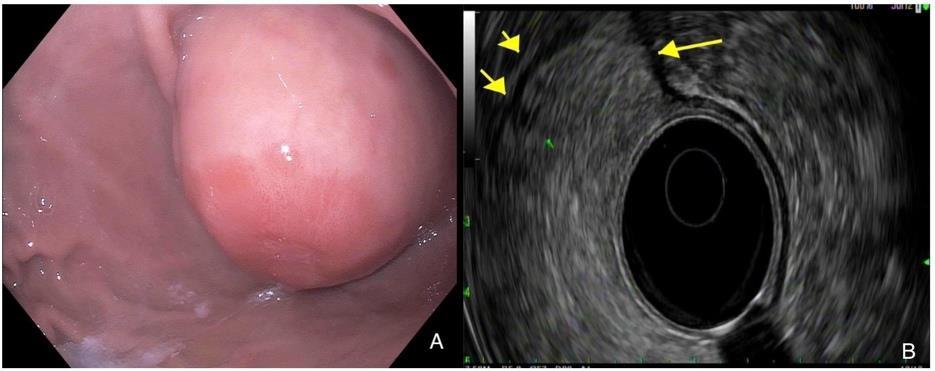

THE CASE OF THE PSEUDO-PSEUDO POLYP: FIRST REPORTED CASE OF A SPINDLE CELL SARCOMA AT AN ILEOCOLONIC ANASTOMOSIS

Ines Varela Knorr1, Jennifer Claytor2, James Marion2

1Mount Sinai Morningside-West Hospitals, Icahn School of Medicine at Mount Sinai, New York, NY, United States;

2Mount Sinai Hospital, Icahn School of Medicine at Mount Sinai, New York, NY, United States

To be presented at the Digestive Disease Week (DDW) Annual Meeting to be held in Washington, D.C., United States from May 18-21, 2024.